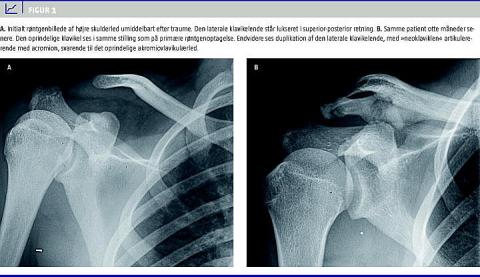

Objektivt fandtes kraftig hævelse og palpationsømhed af laterale klavikelende. Initiale røntgenbilleder af højre skulder blev tolket som komplet AC-luksation, og patienten behandlet med løs mitella

(Figur 1A ).

Seks måneder senere havde patienten genoptaget håndboldspil, men havde fortsat lette smerter i skulderen. Der fandtes på dette tidspunkt tvedelt lateral klavikelende samt smerter ved udadrotation på abduceret skulder.

Røntgenbilleder (og supplerende computertomografi (CT)) viste todelt lateral klavikelende, med én ende artikulerende med acromion, og den anden pegende bagud lateralt (Figur 1B). Den oprindelige posteriore klavikelende blev grundet kosmetiske og funktionelle gener fjernet operativt cirka otte måneder efter traumet. Ved opfølgende kontrol fandtes skulderen og armen at fungere normalt.